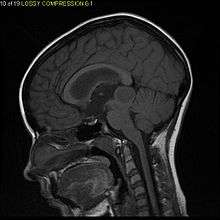

Pilocytic astrocytoma or juvenile pilocytic astrocytoma or cystic cerebellar astrocytoma (and its variant juvenile pilomyxoid astrocytoma) is a brain tumor that occurs more often in children and young adults (in the first 20 years of life). They usually arise in the cerebellum, near the brainstem, in the hypothalamic region, or the optic chiasm, but they may occur in any area where astrocytes are present, including the cerebral hemispheres and the spinal cord. These tumors are usually slow growing and benign.[1] The neoplasms are associated with the formation of a single (or multiple) cyst(s), and can become very large.

Pilocytic astrocytomas are often cystic, and, if solid, tend to be well-circumscribed. It is characteristically easily seen on CT scans and MRI.

Usually—depending on the interview of the patient and after a clinical exam which includes a neurological exam, and an ophthalmological exam—a CT scan and or MRI scan will be performed. A special dye may be injected into a vein before these scans to provide contrast and make tumors easier to identify. The neoplasm will be clearly visible.

Macroscopically, an astrocytoma is a mass that looks well-circumscribed and has a large cyst. The neoplasm may also be solid.